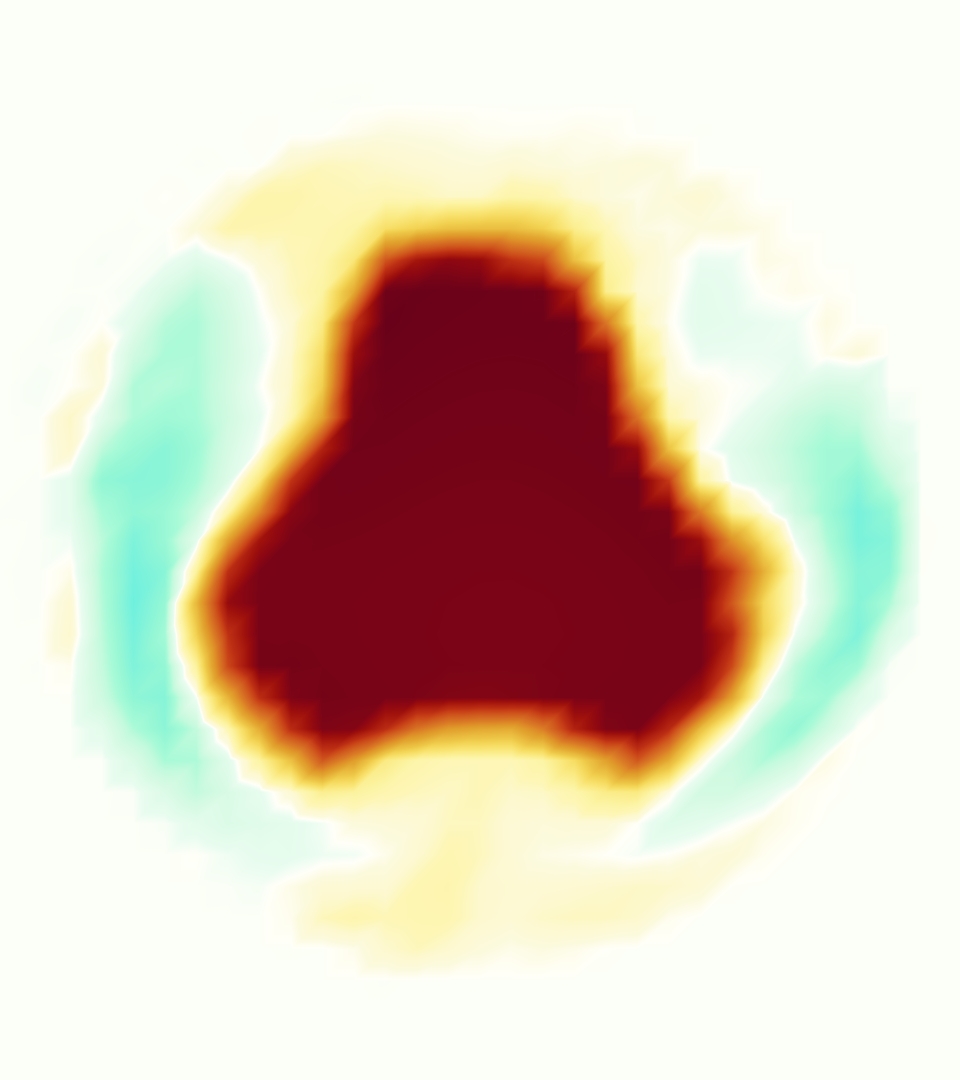

Slice views of the (axial) component of fluid velocity in the axial plane, orthogonal to the flow direction, show that the simulation replicated the development of the jet over the cardiac cycle. At each phase, the simulation matched the forward speed of the core of the jet and the locations of reverse flow back towards the valve annulus. While there are some differences in the shape of the jet at certain phases and locations, the simulation clearly produced the general dynamics of the cardiac cycle that are seen in the experiment.

At = 0, the axial slice directly at the valve annulus shown in columns 1 and 2 in Figure 6, there was excellent agreement between the simulation and experiment over the cardiac cycle in the speed and shape of the jet through the valve. In both cases, the axial velocity increased as the flow accelerated during systole and the valve leaflets opened, then decreased during diastole with slight negative velocity before the valve leaflets were fully closed. The forward flow through the valve annulus did not form a full circle, but rather developed a triangular shape with a point of the triangle forming along the interior curve of the vessel, at the bottom of the axial slices. At = 0, the points of this triangular jet shape aligned with the commissures of the valve. This shape persisted during peak systole and was well-matched by the simulation.

The axial slice = 0.625 cm, shown in columns 3 and 4 in Figure 6, cut through the support scaffolding of the valve and the leaflets when they are open. In the experimental data, the shape of the jet changed as it moved downstream. A triangular shape occurred, but the points were then aligned with the middle of each open leaflet as opposed to the commissures. Those points were also more rounded than they were at = 0. The peak velocity of the jet was faster at = 0.625 cm than at = 0, as the flow accelerated through the open valve leaflets. The simulation produced these features at = 0.625 cm. The triangular shape of the jet shifted similarly, and its speed increased compared to the upstream slice. As the flow decelerated into diastole, the jet shape remained roughly triangular but diminished in intensity before disappearing after valve closure.

The jet continued to develop at = 1.25 cm, an axial slice immediately downstream of the valve scaffolding and open leaflets, shown in columns 5 and 6 in Figure 6. In the experimental data, the points of the triangular jet shape extended further towards the vessel wall. In addition, regions of reversed flow developed in the locations downstream of the commissures, resulting in curved sides to the shape of the jet. Each tip of the jet was unique, due to variations in the individual leaflets in the physical bioprosthetic valve. These variations are apparent in the velocity fields, possibly because the jet edges are similar enough cycle to cycle that irregularities are still being captured even with phase averaging. Further discussion of these features can be found in Schiavone et al. [39], which showed that the jet tip shapes occurred in different pulmonary anatomies, demonstrating that they were likely due to inherent properties of each leaflet. The leaflets in the mathematical model of the valve are identical, so these nuances in leaflet variation could not be replicated. The simulation did capture some of the extension of the tips of the jet, as they were closer to vessel wall at slice = 1.25 cm than = 0.625 cm. The curves in the triangular sides of the jet were also present in the simulation, though they were less pronounced than the experimental data. At both = 0.625 cm and = 1.25 cm, the jet shape in the simulation was smoother than the jet in experiment. It is possible that the free edges of the leaflets in the mathematical model are not fully replicating the behavior of the physical leaflets of the bioprosthetic valve, in particular the amplitude or frequency of leaflet flutter, leading to the variations seen in the jet shape at = 1.25 cm downstream of the leaflet edges. The simulation, however, does capture the key features of the triangular shape and speed of the jet. Overall, qualitative comparisons demonstrated that the simulation reproduced key features of the flow during systole and diastole.